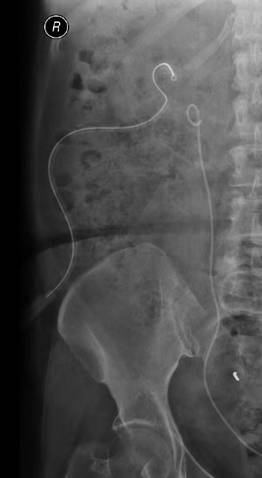

术前X线片 术前CT片

术后X线片 术后CT片